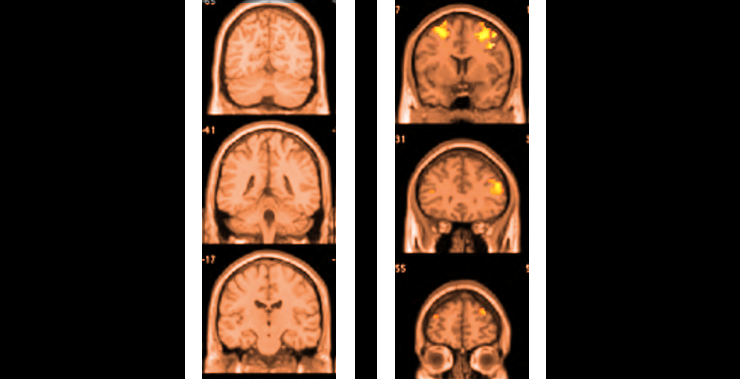

Here’s a fairly well balanced article about the current research into the effects of marijuana on the human brain.

Summary:

• Bad for developing brains

• Has some nasty short -term effects in adolescents that may result in worse life outcomes

• Possibly makes PTSD worse

• Potentially good for anxiety and depression

• Potentially good for older people who start smoking at an advanced age

That’s a pretty far cry from “all this research is coming out about the neurological damage associated with marijuana”. Basically kids/adolescents and people with certain psychological issues should avoid it which is pretty much every drug.